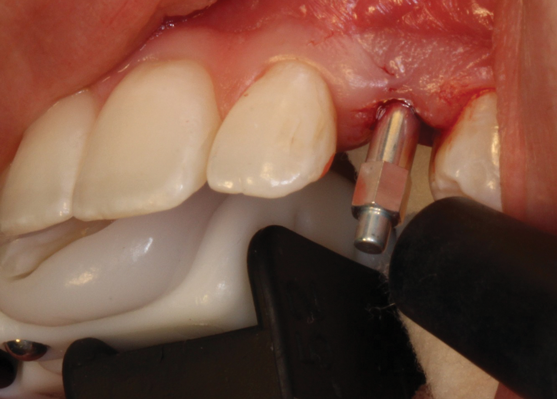

(35.) An implant being inserted into the prepared osteotomy of a patient who presented for the replacement of the maxillary left central incisor.

Figure 35

(36.) The implant’s primary stability was assessed by RFA, and the ISQ value greater than 65 was used to determine that immediate provisionalization was indicated.

Figure 36

(37.) The implant’s primary stability was assessed by RFA, and the ISQ value greater than 65 was used to determine that immediate provisionalization was indicated.

Figure 37

(38.) The opaqued titanium provisional abutment was gently tightened onto the implant.

Figure 38